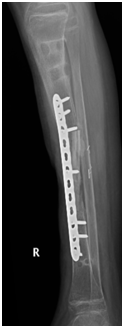

Three month later, the external fixator was removed; back slab was applied for 10 day to decrease the possibility of pin site infection. Final augmentation of the grafting was done by fibular allograft and fixed by 12 whole LCP. The nerve grafting performed (Figures 5a-5c). Two months later, the patient was seen in the clinic, he was able to move his ankle, radiography of the tibia demonstrated a remarkable filling of the gap by bone (Figures 6a-6d).

• Figure 5a-c During fixation of the tibia with DCP plate and insertion of fibular graft and grafton.

• Figure 6a-c Postoperative follow up 2 months later.